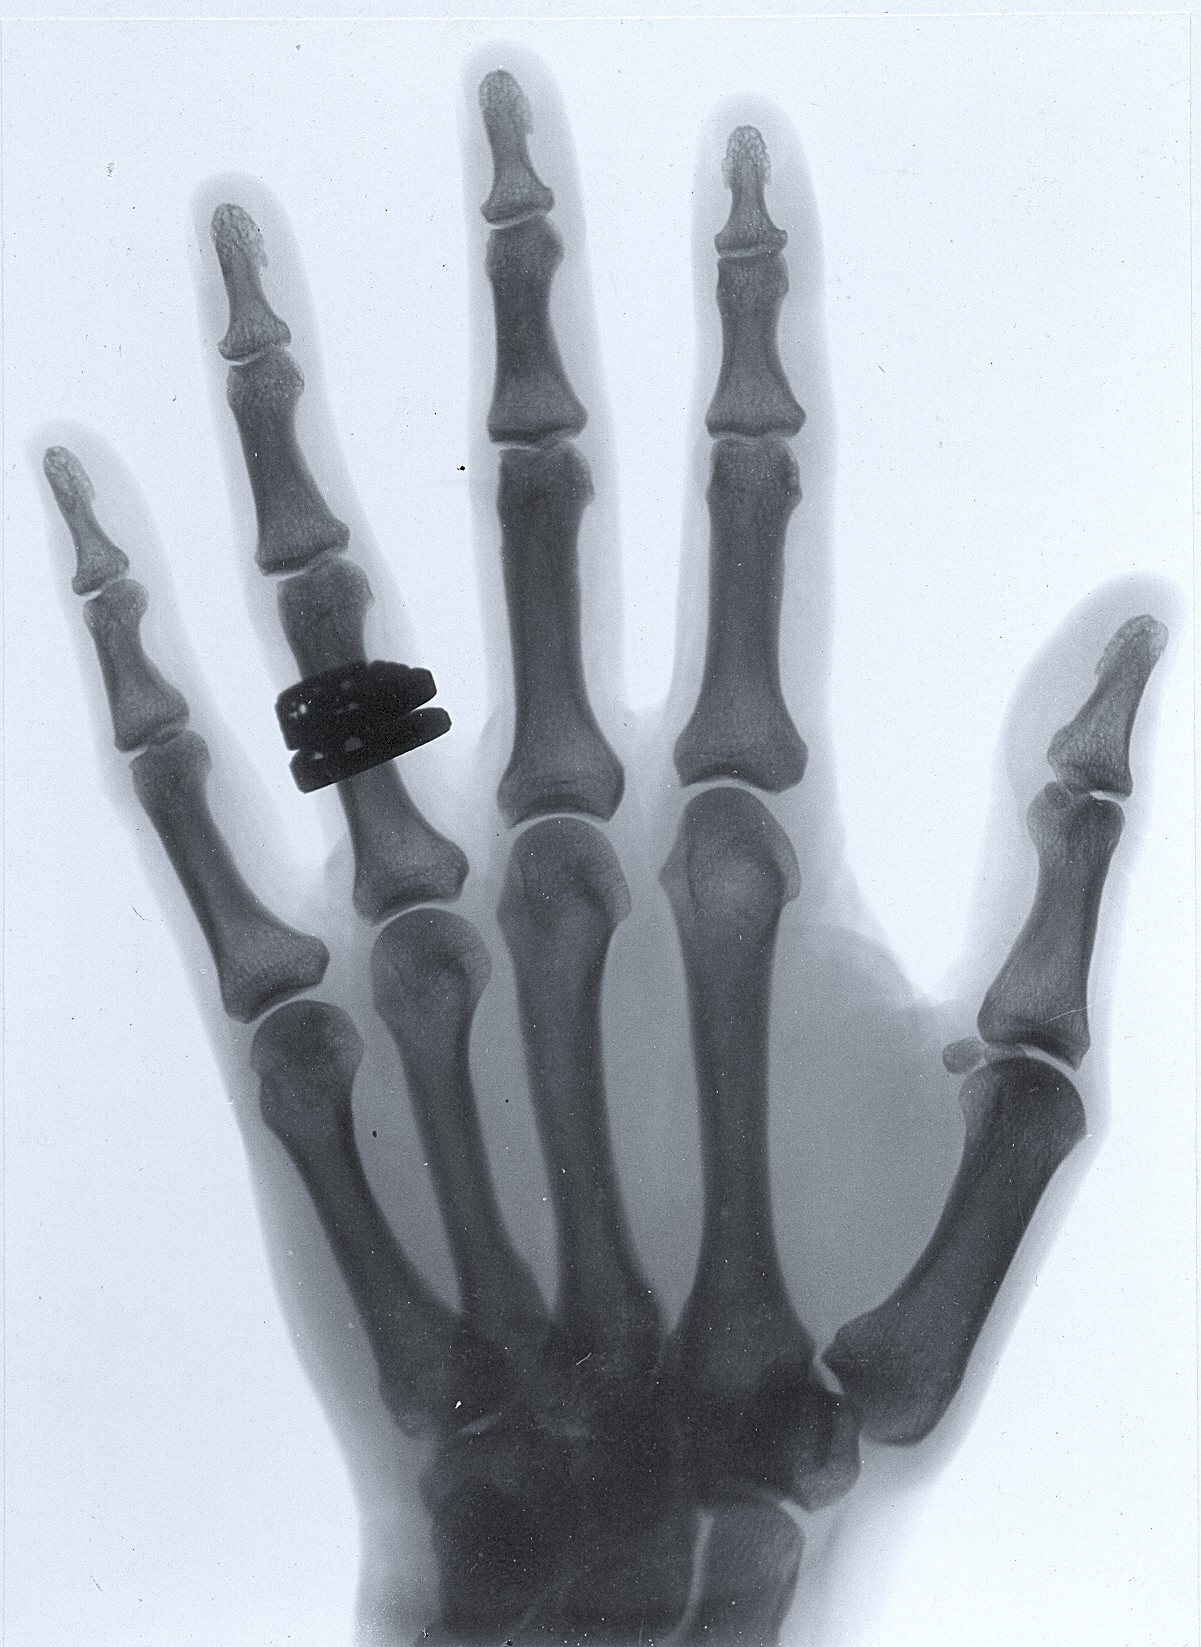

Photography had been around for some time but x-rays and radio-activtity were a new development in the late 1890s. Salomons was immediately interested. We don't know exactly when he produced his experimental images - of a human hand (see right), and a mouse , but possibly in the early 1900s. The extra facilities built alongside the lecture theatre included a dedicated x-ray room.

One of Salomon's experiments with X-rays - human hand. DSH.M.00523a..